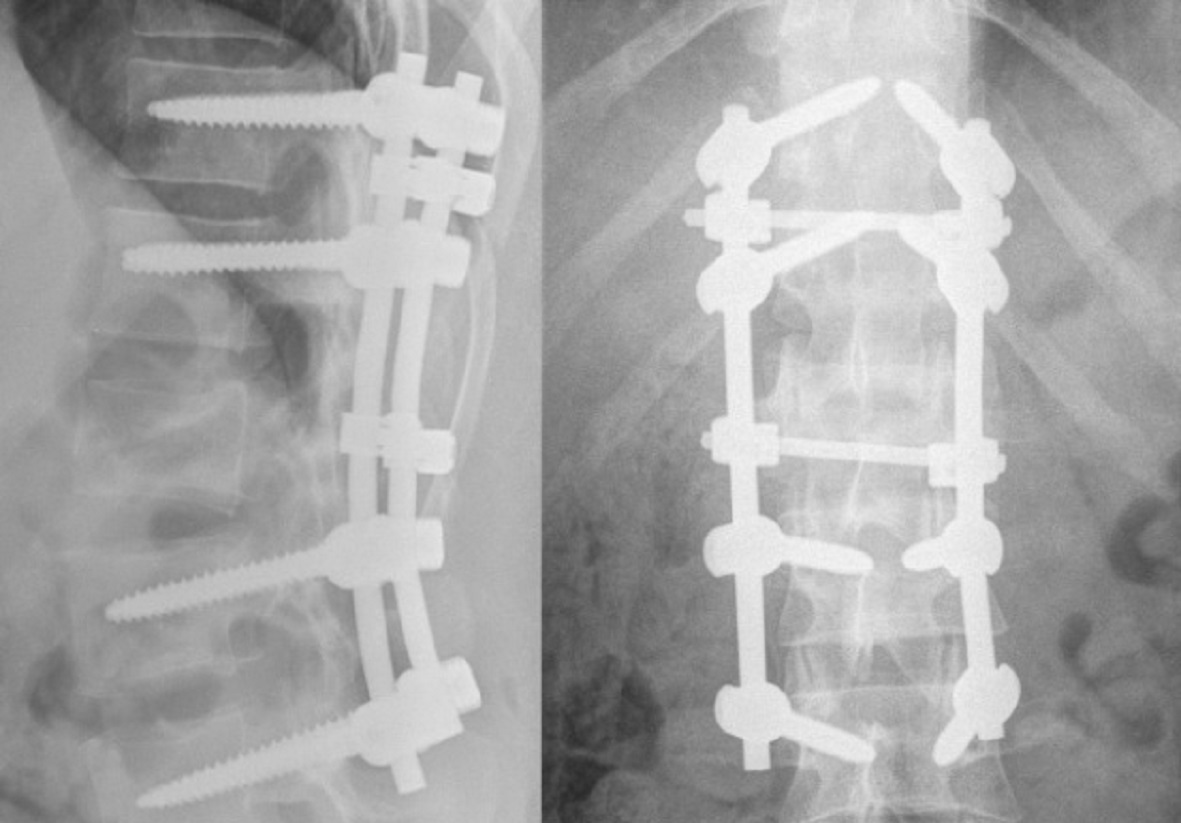

Красноярец катался на плюшке и сломал позвоночник

Ему проведут две операции